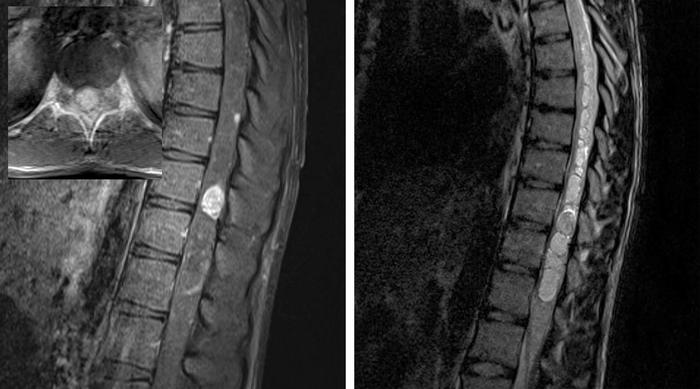

3:图中所示为一名VHL患者胸髓血管母细胞瘤伴多发髓内病变。注意巨大肿瘤位于脊髓偏心位置且伴一大型囊肿。